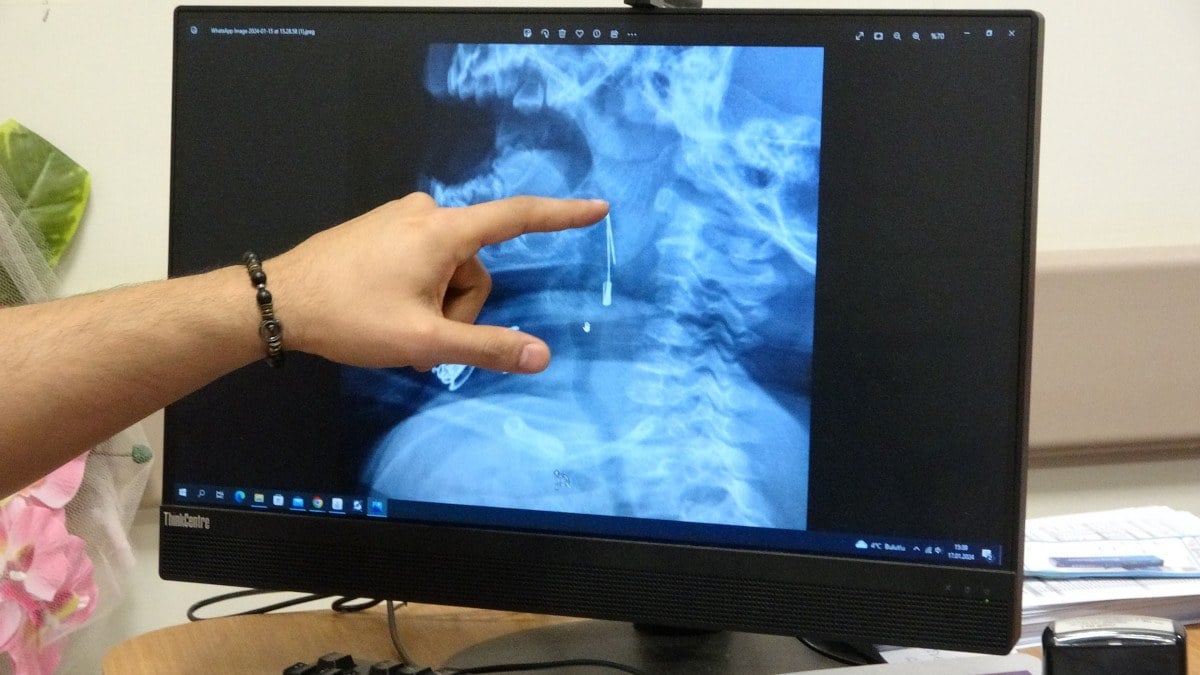

Öksürmeye başlayan minik çocuğun, hastanede çekilen röntgen sonucu çengelli iğneyi yuttuğu fark edildi.

8 aylık bir bebek, Bitlis’in Güroymak ilçesinden tarafımıza danışıldı. Güroymak ilçesinde çekilen röntgen sonucunda çengelli iğnenin soluk borusunun girişinde olduğunu teyit ettik. Yapılan müdahaleler sonucunda çengelli iğneyi çıkardık. Çıkardıktan sonra iki saat kadar gözlem altında tuttuk hastamızı. Daha sonrasında herhangi bir komplikasyonla karşılaşmadık ve sorunsuz bir şekilde taburcu ettik.